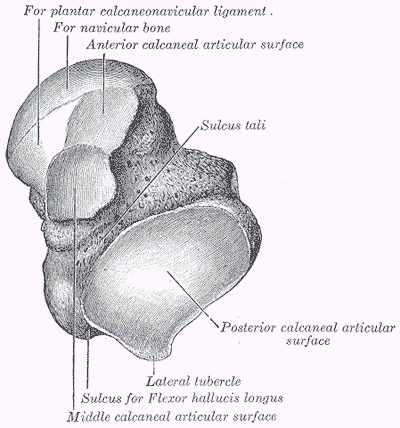

What tarsal(s) does the talus articulate with?

navicular (articulates at the head of the talus)

The trochlear surface of the talus articulates ___, ___, and ___

superiorly with the tibia

laterally with the fibula

inferiorly with the calcaneus

How many articular surfaces does the talus have inferiorly to articulate with the calcaneus?

3 (anterior, middle, posterior)

Label the 3 surfaces of the talus that articulate with the calcaneus